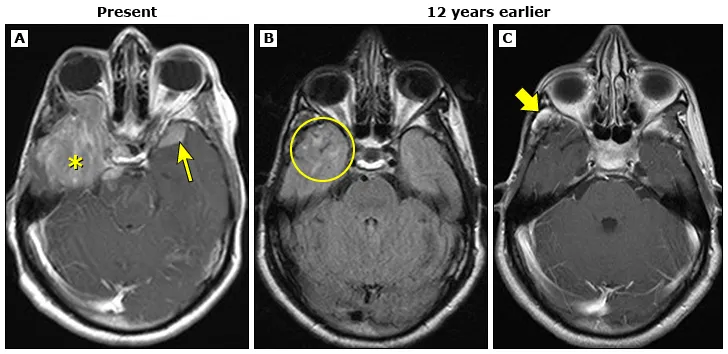

10岁时,患者为治疗横纹肌肉瘤接受了高剂量放疗。未曾预料,这一挽救生命的治疗措施在脑内埋下隐患。12年前的影像(图B-C)已显示早期迹象:右颞叶放疗后白质损伤(圆圈所示)及原肿瘤区增生肉芽组织(粗箭头所示)。

如今,一巨大脑膜瘤(图A)被发现,表现为大型轴外强化肿块,侵犯右侧眶内、鞍区及桥前池;左侧蝶骨大翼另见一较小硬脑膜基底病灶(箭头所示)。右颞叶病灶经病理证实为脑膜瘤。该情况并非偶然,而是二十七年前放疗的结果。